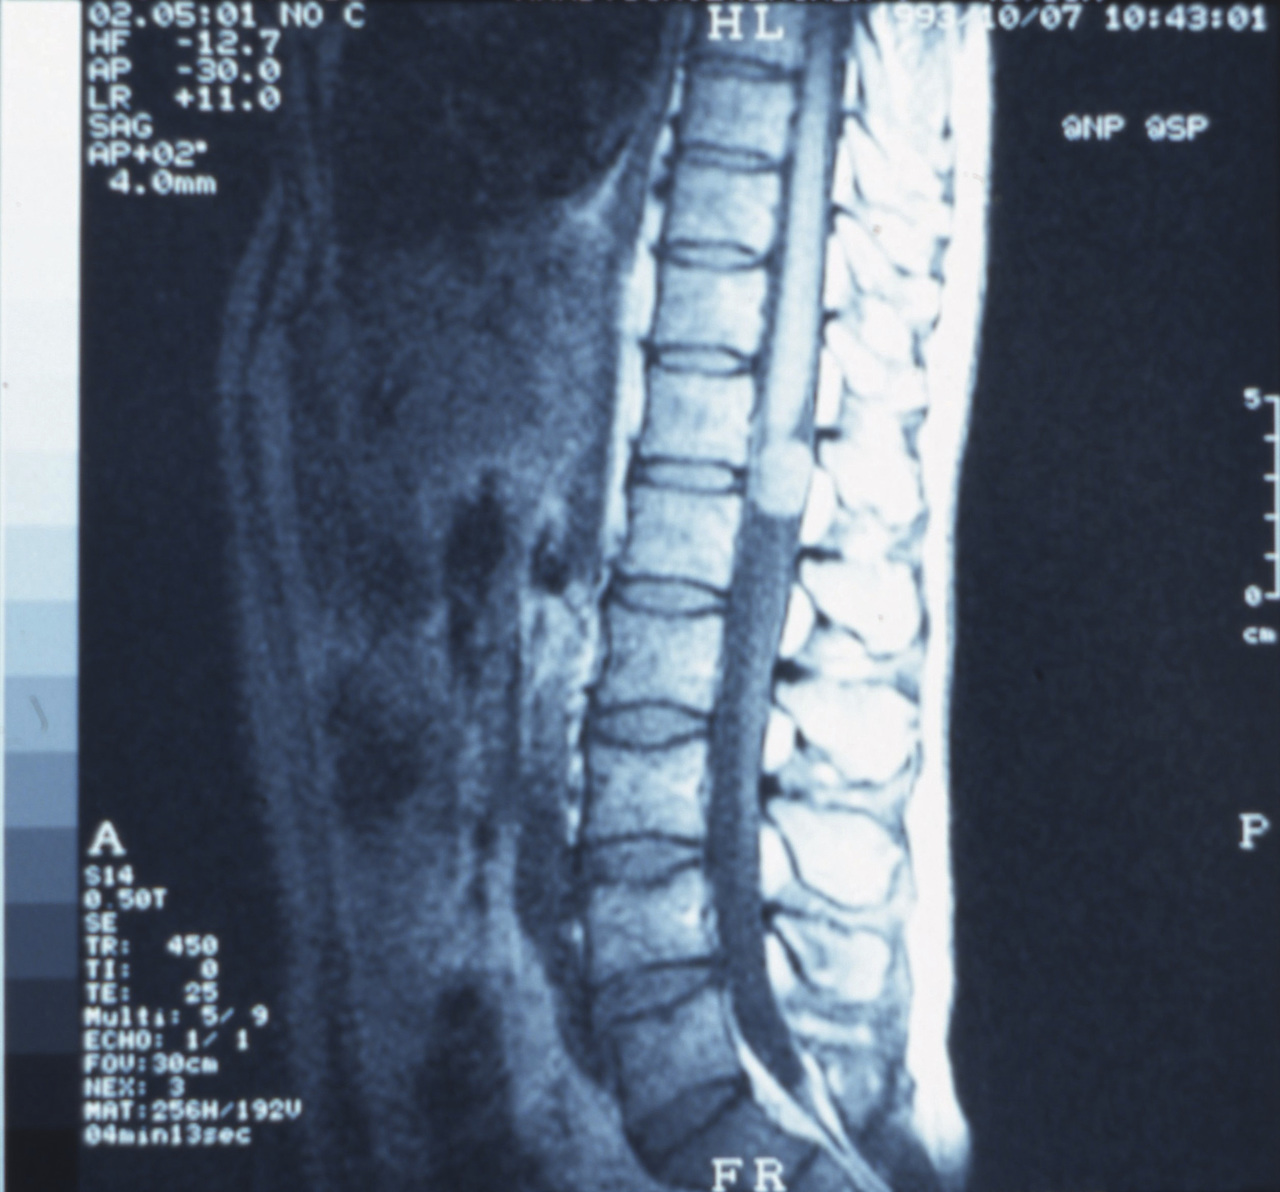

Il s’agit d’un neurinome.

Le neurinome ou schwannome survient le plus souvent chez l’homme, vers la quarantaine. Classiquement, le symptôme inaugural est constitué de douleurs rachidiennes très intenses, volontiers nocturnes, résistant aux antalgiques. Le schwannome se développe dans l’espace périmédullaire à partir d’une racine. Il peut être malaisé à distinguer avec certitude d’un méningiome en IRM. Rarement son développement est à la fois intra- et extracanalaire, donnant un aspect de tumeur « en sablier ». Le foramen intervertébral apparaît alors élargi sur les radiographies standard. À noter, enfin, l’association possible à une neurofibromatose,qui ne doit pas être méconnue.